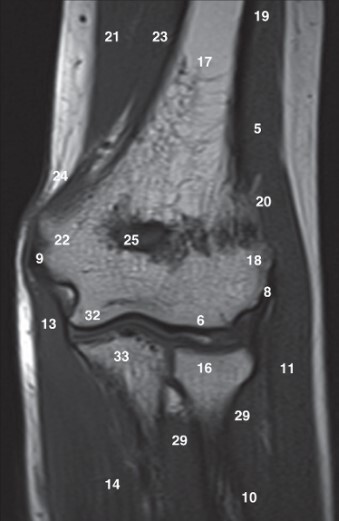

9

Q

Label 6,16,17,18,22,25,32

A

6=Capitulum of lt. humerus

16=Head of lt. radius

17=Lt. Humerus

18=Lateral condyle (lt. humerus)

22=Medial condyle (rt. humerus)

25=Olecranon fossa of lt. humerus

32=Trochlea of lt. humerus